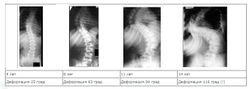

Рентгенологическая классификация (по В. Д. Чаклину):

- 1 степень сколиоза. Угол сколиоза 1° — 10°.

- 2 степень сколиоза. Угол сколиоза 11° — 25°.

- 3 степень сколиоза. Угол сколиоза 26° — 50°.

- 4 степень сколиоза. Угол сколиоза > 50°.;

При решении об освобождении от военной службы учитывается степень сколиоза, установленная по рентгенограммам (см. выше).